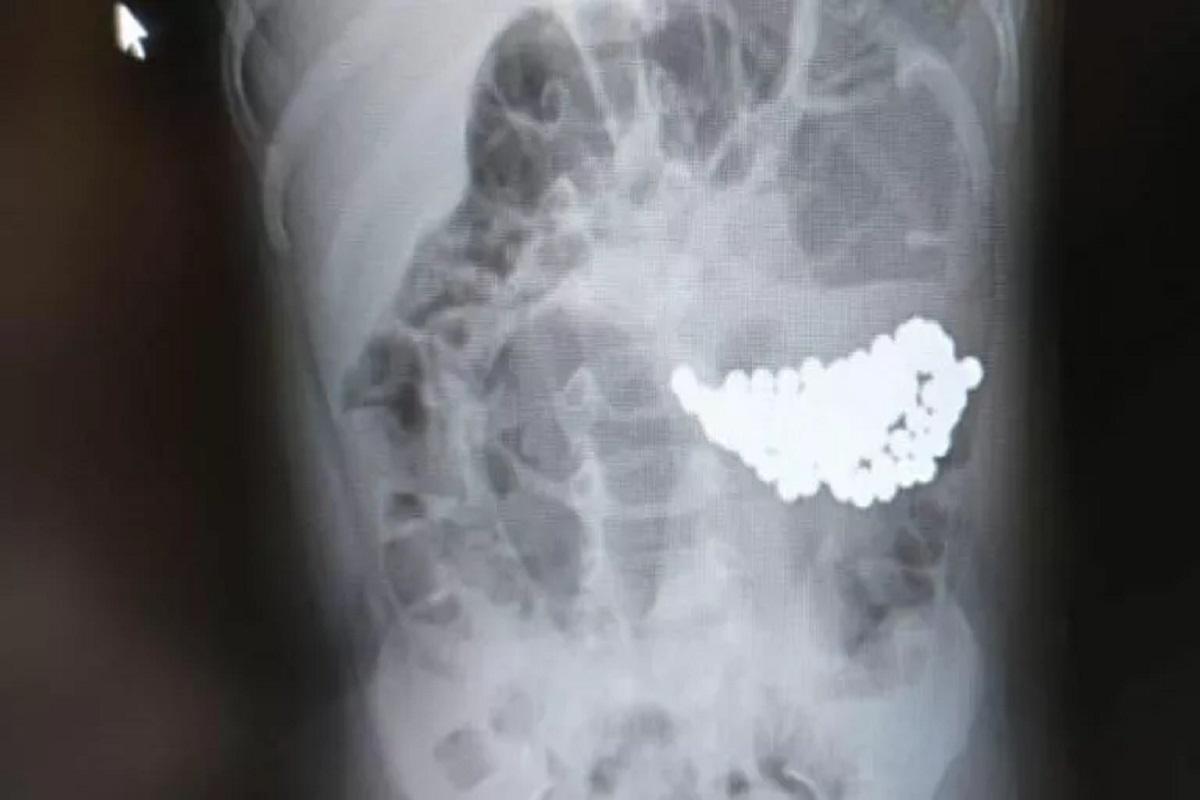

После обследования выяснилось, что причиной недомогания стала кишечная непроходимость, вызванная большим скоплением инородного тела. Магнитные шарики вызвали конгломерат, который сдавливал стенки кишечника.